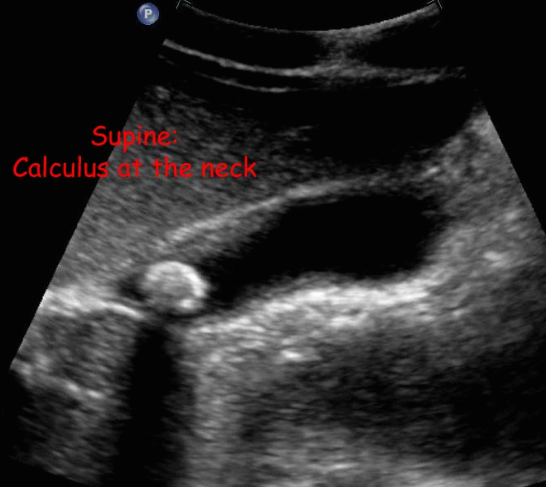

- 환자 체위에 따라 움직임 (rolling stone sign)